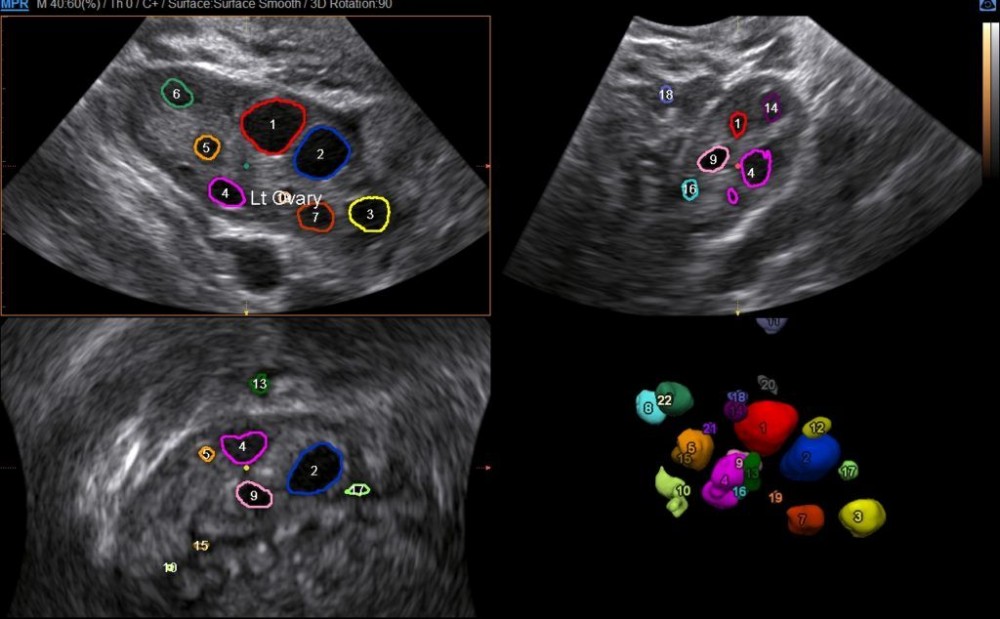

În modul 3D/4D volumetric:

• Sistemul captează un volum complet al ovarului.

• Algoritmii AI segmentează spațiul și identifică individual foliculii antrali din interiorul volumului, indiferent de orientarea acestora.

• Se generează o imagine 3D cu reprezentarea fiecărui folicul, contur colorat și dimensiuni măsurate automat.

• Exemplu: GE SonoAVC™ follicle sau Samsung 5D Follicle™ – oferind o hartă volumetrică interactivă cu listă automată de valori pentru fiecare folicul detectat.

În cazul semi-automatizării, medicul:

• validează sau ajustează manual contururile detectate de AI (dacă este necesar),

• poate adăuga sau elimina foliculi în mod interactiv,

• primește un raport complet cu numărul de foliculi, diametre, volume și poziții.